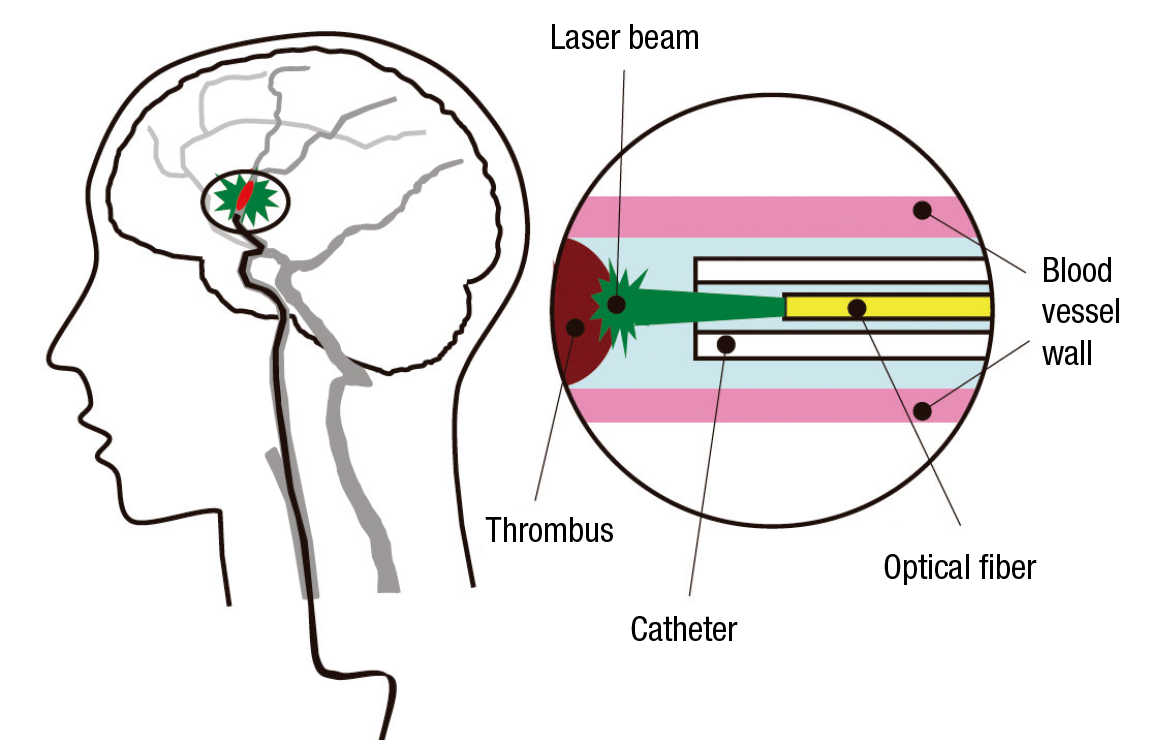

Hamamatsu Photonics has also developed many world-class products in the field of lasers, in which it started R&D activities in the 1990s. Recently it became the first in the world to develop a laser thrombolysis technology for treatment of cerebral thrombi—blood clots in the brain that cause strokes—which works as follows: A catheter encasing an optical fiber is inserted via a femoral artery and extended to the location of the thrombus, and a green laser beam at a wavelength of 532 nanometers is directed at the site. At this wavelength, the beam is not absorbed by the blood vessel wall but affects only the thrombus, which it dissolves with almost no risk of damage to the blood vessel walls. Since the tip of the catheter is thin, with a diameter of only 0.8 millimeters, and flexible, it can be used for treatment in blood vessels of around 1 mm in diameter, which are hard to treat with existing devices for suction-purpose catheterization. In this way it offers hopes for expanding the scope of cases that can be treated.

Hamamatsu Photonics has been conducting its research in collaboration with a local hospital and Hamamatsu University School of Medicine. Dr. Hiroyuki Okada, who is responsible for laser thrombolysis R&D at the company’s Central Research Laboratory, explains, “We had a hard time reconciling the different mind-sets of the medical treatment staff and the engineers.” The engineers wanted to create a device allowing fine-tuning of irradiation times, power, and other settings, while the medical staff wanted a simple-to-operate device that would let them concentrate on treatment. He says, “We put the wishes of the medical staff first and made adjustments, such as minimizing the number of operating buttons, while aiming for high reliability.” The effectiveness and safety of laser thrombolysis technology has been confirmed in experiments on animals, and it is planned to start clinical tests on humans this spring; the aim is to create a product for practical use in five years.

The tip of the catheter is a mere 0.8 mm in diameter.